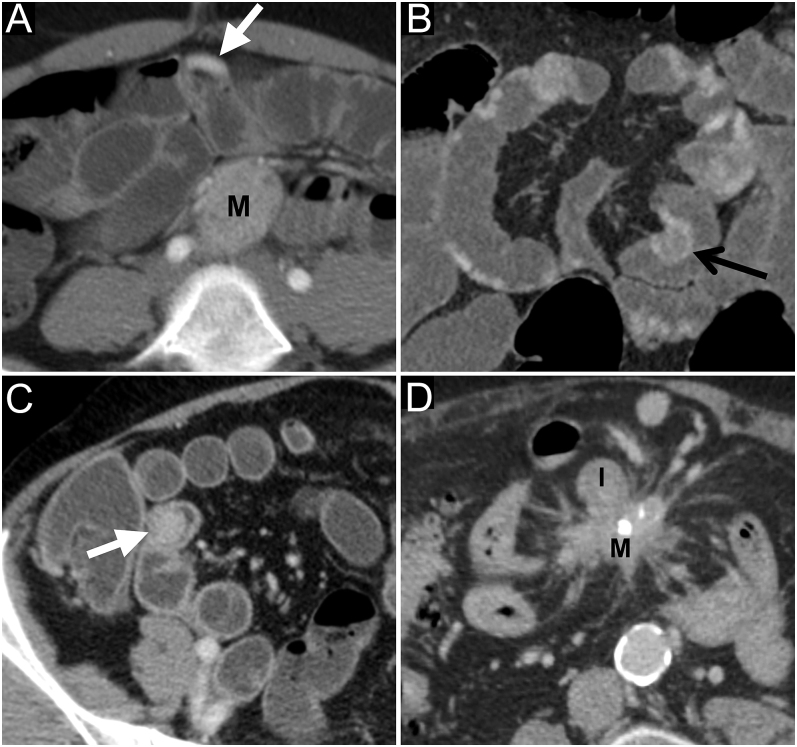

The mesenteric extension of small neuroendocrine tumors is the surgical limiting factor because of the risk of postoperative short bowel syndrome due to superior mesenteric artery involvement. Recent pathological studies have shown that this vascular involvement is due to mesenteric tumor deposits, differentiated from lymph node metastases. The aim of this study was to evaluate the performances of computed tomography (CT) for the surgical planning of small intestine neuroendocrine tumors. This was a retrospective observational study, and all patients undergoing surgery for small intestine neuroendocrine tumor between January 2014 and March 2019 were included. Preoperative CTs were reviewed, blinded from surgical and pathological data, by two radiologists. Diagnostic accuracy and interobserver reliability analysis were performed. We included 45 patients (mean age: 61 years (28-84 years); 23 men). The CT sensitivity to identify the mesenteric mass was 97% (37/38) with a ĸ of 0.73. The positive predictive value of CT to anticipate a right colic resection was 86% (18/21). The negative predictive value of CT was high (97% (34/35) to 100% (35/35)) for duodenal resection (ĸ = 0.78). Regarding retropancreatic lymph node invasion, the CT sensitivity was poor (24%, 4/17), with a high ĸ (0.88). The level of involvement by the mesenteric mass was correlated with the length and the percentage of the remaining small bowel. CT is essential for the surgical planning of small intestine neuroendocrine tumors, being accurate in defining the mesenteric tumor deposits, allowing one to anticipate, with a good reproducibility, the length and percentage of the remaining small bowel and the necessity for a right colectomy.